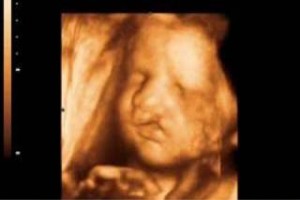

El programa fue diseñado para llevar de la mano al participante y ofrecerle herramientas que le permitan hacer una evaluación radiológica atinada, lo cual lo llevará a un diagnóstico que por ende arrojará el tratamiento idóneo. El énfasis se ha dado en la metodología diagnóstica, que es por inducción, así como el manejo del paciente, para crear una conciencia responsable y humana entre los que se dedican o quieren iniciarse en la práctica de la ultrasonografía. Dado a que existe una aplastante demanda de estudios de ultrasonido ante el insuficiente número de médicos radiólogos certificados, además de que el servicio de rayos x en México ha sufrido de ineficiencia en la aplicación del estudio y elaboración diagnóstica de la patología, la labor de este curso es formar de manera profesional a los médicos para que cubran y aminore en gran medida este problema que habita en el sector de salud.